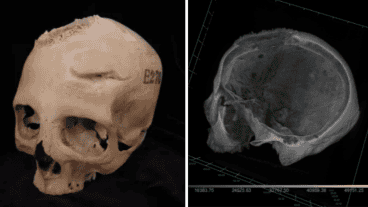

Científicos encontraron una serie de marcas en un antiguo cráneo egipcio, las cuales sugieren una intervención quirúrgica oncológica en el Egipto de hace 4.300 años. Los hallazgos provienen del examen del cráneo de un hombre de unos 30 años del año 2500 a.C. y de una mujer de unos 50 años del año 500 a.C.

Si bien ambos tenían huesos dañados, lo que demuestra que probablemente padecían cáncer cerebral, también tenían marcas de herramientas. Los investigadores dijeron que eran una prueba de que los curanderos intentaron operar tumores cerebrales, según publicó el medio británico The Sun.

El profesor Edgard Camaros, de la Universidad de Santiago de Compostela, en España , dijo: "Esta es una evidencia única de cómo la medicina egipcia antigua habría intentado abordar o explorar el cáncer. Es una nueva perspectiva extraordinaria para comprender la historia de la medicina".